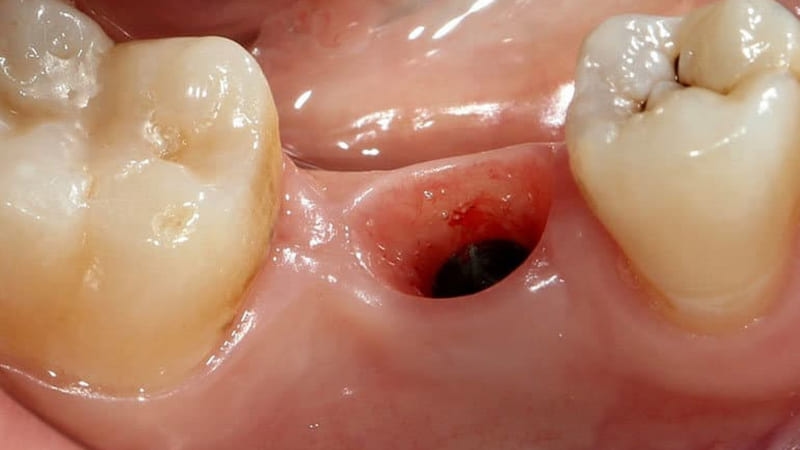

Nhổ răng khôn để lại lỗ: Bí quyết giảm sưng đau hiệu quả

Việc phát hiện một lỗ hổng tại vị trí răng khôn vừa nhổ là điều khiến nhiều người lo lắng. Tuy nhiên, đây là một phần hoàn toàn bình thường của quá trình lành thương. Tình trạng nhổ răng khôn để lại lỗ sẽ sớm được khắc phục nếu bạn hiểu rõ nguyên nhân và có cách chăm sóc đúng đắn. Bài viết này sẽ là cẩm nang toàn diện, cung cấp mọi thông tin bạn cần biết để xử lý vấn đề này một cách an toàn và hiệu quả.

5. Tầm quan trọng của cục máu đông sau khi nhổ răng khôn

Ngay sau khi nhổ răng, một cục máu đông sẽ hình thành và lấp đầy huyệt ổ răng. Đây là yếu tố cực kỳ quan trọng, có vai trò như một “nút chặn sinh học” tự nhiên, giúp:

– Cầm máu: Ngăn không cho máu tiếp tục chảy từ vết thương.

– Bảo vệ: Che chắn cho phần xương hàm và các đầu dây thần kinh bên dưới khỏi sự tấn công của vi khuẩn và vụn thức ăn.

– Thúc đẩy lành thương: Tạo ra một môi trường thuận lợi để các tế bào mới phát triển, hình thành mô hạt và dần dần lấp đầy lỗ hổng.

Bảo vệ cục máu đông này trong 24-48 giờ đầu tiên là ưu tiên hàng đầu để quá trình lành thương sau khi nhổ răng khôn để lại lỗ diễn ra suôn sẻ.